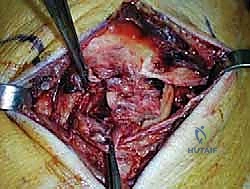

الخطوة الثانية: تنظير المفصل التشخيصي والعلاجي (Arthroscopy)

قبل فتح الجانب الإنسي، يقوم الدكتور هطيف بإدخال كاميرا دقيقة (منظار 4K) من خلال ثقوب صغيرة جداً في مقدمة الكاحل. هذه الخطوة حاسمة لتنظيف المفصل من أي أنسجة ملتهبة، وإزالة أي شظايا عظمية أو غضروفية حرة، ومعالجة أي تقرحات في سطح عظمة الكاحل ناتجة عن عدم الاستقرار.

الخطوة الرابعة: تقييم وإصلاح رباط الدالية (Repair vs. Reconstruction)

بمجرد الوصول إلى رباط الدالية، يتم تقييم درجة التلف:

* الإصلاح المباشر (Direct Repair): إذا كانت أنسجة الرباط الممزقة ذات جودة جيدة (عادة في الإصابات الحديثة)، يقوم الدكتور هطيف بخياطتها مباشرة. يستخدم خطاطيف تثبيت عظمية (Suture Anchors) صغيرة جداً ومصنوعة من مواد متوافقة حيوياً (تذوب مع الوقت أو من التيتانيوم) لغرس الخيوط القوية في عظمة الكعب الإنسي، ثم يتم سحب الرباط الممزق وتثبيته بقوة في مكانه التشريحي الأصلي.